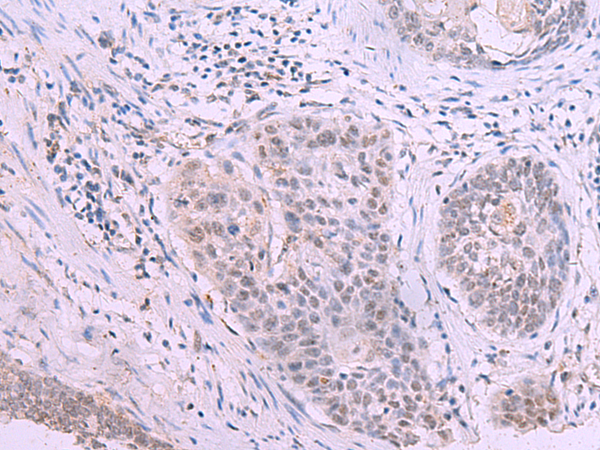

分类: 科研抗体货号: P13570别名: B7y; B7H7; B7-H5; B7-H7应用: IHC反应种属: Human